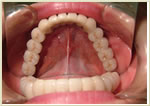

症例2 63歳 女性 画像拡大

治療前 治療後